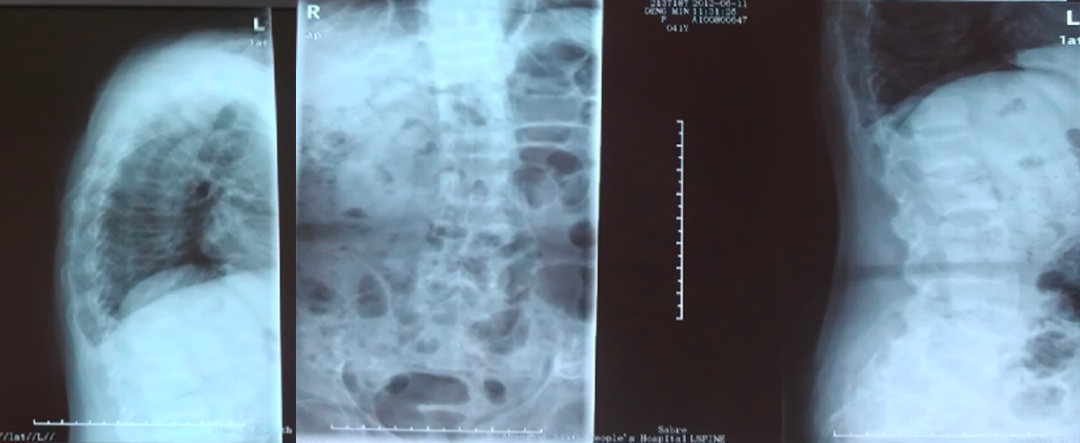

2、利用X线平片发现椎体压缩性骨折(每个医院包括社区均有):

脆性骨折是指受到轻微创伤或日常活动中即发生的骨折,老年男性椎体骨折的患病率与女性相当,椎体骨折的防治在男女两性同等重要。

常规进行X线胸腰椎正侧位摄片漏诊率高,患病率高(上海社区60岁以上17%,建议对50岁以上腰背部疼痛者常规摄片,及早发现椎体骨折。

二、骨质疏松症如何进行影像学检查

X线平片是检出脆性骨折,特别是胸、腰椎压缩性骨折的首选方法。常规胸、腰椎X线侧位摄片的范围应分别包括胸4至腰1和胸12至腰5椎体,基于胸、腰椎侧位X线影像并采用Genant目视半定量判定方法,椎体压缩性骨折的程度分类如下:

X线检查:胸腰椎多发压缩性骨折伴骨质疏松。

诊断:低磷性骨软化(肿瘤性可能)、继发性甲状旁腺功能亢进。

X线检查:L2压缩性骨折椎体骨质疏松,头颅未见异常。